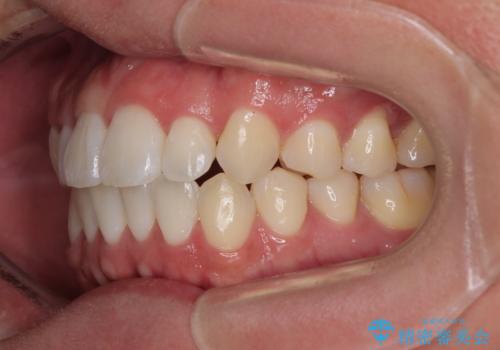

- 前歯の反対咬合などを気にして来院された患者様です。

ワイヤー矯正、マウスピース矯正どちらでも対応可能であったので、ご本人の希望によりインビザラインにて矯正治療を行うこととしました。

毎日の装着時間をしっかりと守ってくださり、1年強の短期間で、あっという間に治療を終えることができました。